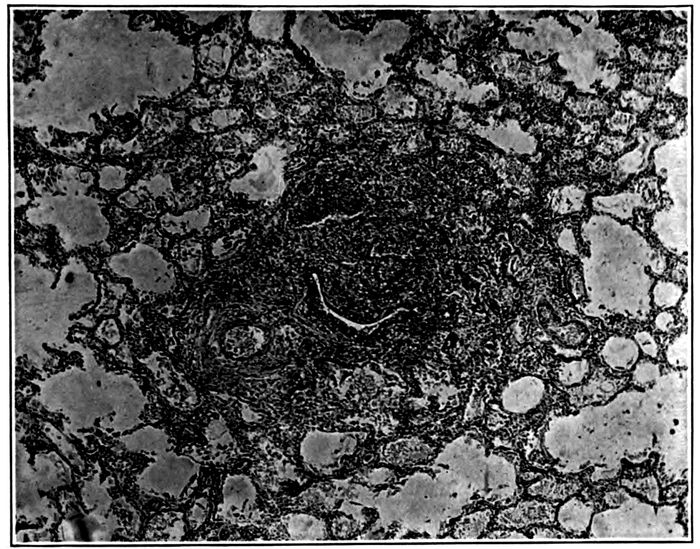

| 10. | Interstitial suppurative pneumonia; interstitial septa are the site of suppuration and lymphatics are distended with purulent fluid; empyema | 211 |

| 11. | Suppurative interstitial pneumonia | 212 |

| 12. | Suppurative interstitial pneumonia | 216 |

| 13. | Suppurative interstitial pneumonia showing a dilated lymphatic | 217 |